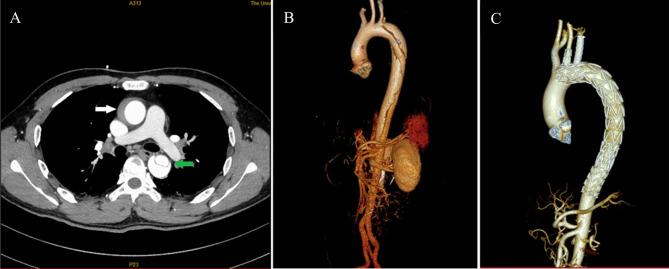

Between June 2019 and June 2021, 21 patients (16 males and 5 females) with a retrograde ascending aortic intramural hematoma, aged 53 ± 14years, received an endovascular repair in our hospital. All cases involved an ascending aortic or aortic arch intramural hematoma. 15 patients had an ulcer on the descending aorta combined with an intramural hematoma in the ascending aorta and 6 patients had typical dissection changes on the descending aorta combined with an intramural hematoma in the ascending aorta. All patients had a successful endovascular stent-graft repair, with 10 cases operated on in the acute phase (<14 days) and 11 cases in the chronic phase (14-35 days).

A single-branched aortic stent graft system was implanted in 10 cases, a straight stent in 2 cases, and a fenestrated stent in 9 cases. All surgeries were technically successful. One of the patients developed a new rupture 2 weeks after surgery and was converted to a total arch replacement. No perioperative stroke, paraplegia, stent fracture or displacement, limb or abdominal organ ischemia occurred. The intramural hematomas started being absorbed on CT angiography images before discharge. There was no incidence of postoperative 30-day mortality, and the intramural hematomas in the ascending aorta and aortic arch were fully or partly absorbed.